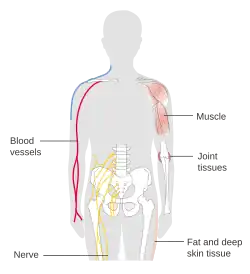

Anatomy

Human anatomy is the study of the shape and form of the human body. The human body has four limbs (two arms and two legs), a head and a neck, which connect to the torso. The body's shape is determined by a strong skeleton made of bone and cartilage, surrounded by fat (adipose tissue), muscle, connective tissue, organs, and other structures. The spine at the back of the skeleton contains the flexible vertebral column, which surrounds the spinal cord, which is a collection of nerve fibres connecting the brain to the rest of the body. Nerves connect the spinal cord and brain to the rest of the body. All major bones, muscles, and nerves in the body are named, with the exception of anatomical variations such as sesamoid bones and accessory muscles.

Blood vessels carry blood throughout the body, which moves because of the beating of the heart. Venules and veins collect blood low in oxygen from tissues throughout the body. These collect in progressively larger veins until they reach the body's two largest veins, the superior and inferior vena cava, which drain blood into the right side of the heart. From here, the blood is pumped into the lungs where it receives oxygen and drains back into the left side of the heart. From here, it is pumped into the body's largest artery, the aorta, and then progressively smaller arteries and arterioles until it reaches tissue. Here, blood passes from small arteries into capillaries, then small veins and the process begins again. Blood carries oxygen, waste products, and hormones from one place in the body to another. Blood is filtered at the kidneys and liver.